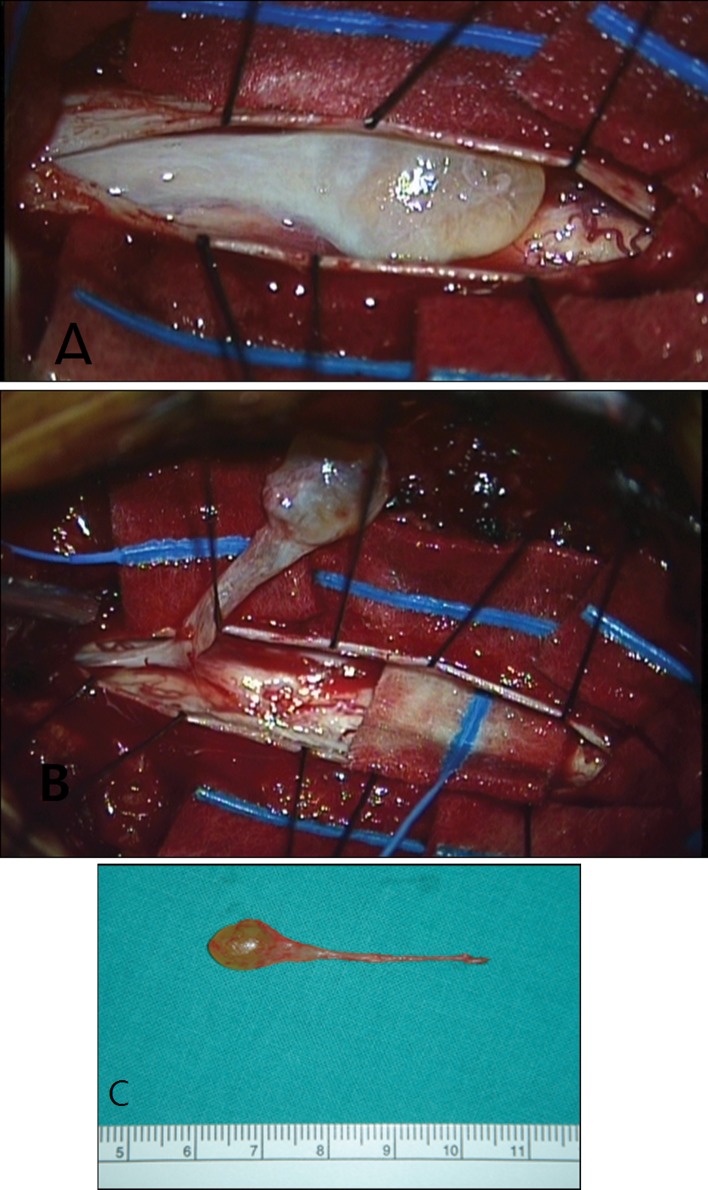

Fig. 2.

a Yellowish cystic mass was noted in the intradural extramedullary space. b Under microscopic magnification, fine arachnoid dissection was performed and the cystic mass was totally removed en-bloc manner. c The cystic mass was 0.5 × 0.5 × 4 cm

Fig. 3.

During and after the dissection, no definite vascular or anatomical abnormal findings of the spinal cord were noted. Only minimal arachnoid thickening was noted around the cystic mass. The remnant of thickened arachnoid was dissected off of the posterior aspect of the cord and was removed